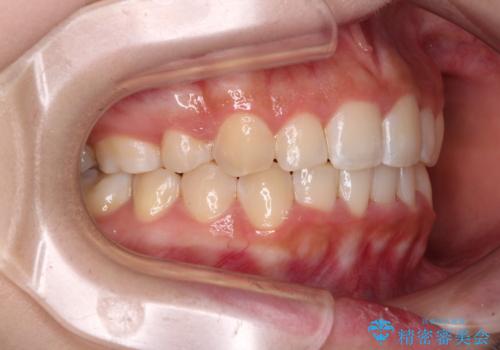

- 上顎の八重歯と、上下前歯のデコボコを気にして来院された患者様です。

奥歯の咬み合わせを見ると、上顎臼歯が下顎に対して前方にあり、叢生改善により口元が突出する顔貌ではなかったため、上顎左右第一小臼歯2本を抜歯し、ワイヤー装置にて矯正治療を行うこととしました。

前歯部のデコボコがなくなったため、歯磨きしやすくなり、非常に清潔な状態になりました。